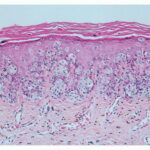

Because not all follicles in a given area are affected, transversely sectioned scalp biopsies may increase the yield of finding the diagnostic histologic features of trichotillomania, including increased numbers of catagen and telogen hairs (most cases) and empty or distorted follicles (greater than 50% of cases) (194). The same study found pigment casts and trichomalacia in less than 50% of cases. When the scalp is also rubbed persistently, epidermal changes of lichen simplex chronicus may be seen in vertical sections. |

being deposited distally as the hair is plucked {194}. Pigment casts are due to injury to the hair matrix, although some authors have theorized that they result from the sudden conversion of anagen to catagen . Hair shaft changes, termed trichomalacia, may be seen. Characterized by diminished size, distorted and odd shape, and irregular pigmentation of the shaft, trichomalacia is additional evidence of trauma to the matrix . Traumatized follicles can also show considerable distortion of the bulbar epithelium and conspicuous hemorrhage . |

Pigment casts, which are clumps of melanin pigment, may be seen in the hair papilla and peribulbar connective tissue. They are also commonly seen in the upper portion of the hair follicle as a result of pigmented matrical cells |

Histopathology. In horizontally sectioned biopsies of trichotillomania uncomplicated by the coexistence of other types of alopecia, the density of hair follicles is normal, as is the terminal-to-vellus hair ratio. The diagnostic finding, when seen, is distorted hair follicle anatomy, without inflammation . Specifically, the pulling of hairs can leave behind empty anagen follicles and "torn-away" follicles, the result of plucked hair shafts that retain parts of the hair matrix and root sheaths . Additional microscopic evidence of traumatic injury was published by Royer et al. as the "hamburger sign," describing a vertically oriented split in the hair shaft containing proteinaceous material and erythrocytes, resembling a hamburger within a bun . Damaged follicles enter the resting phase, leading to an increase in the percentage of catagen and telogen hairs, as high as 75% . Often the hairs do not become normal catagen hairs and appear distorted and abnormal . |